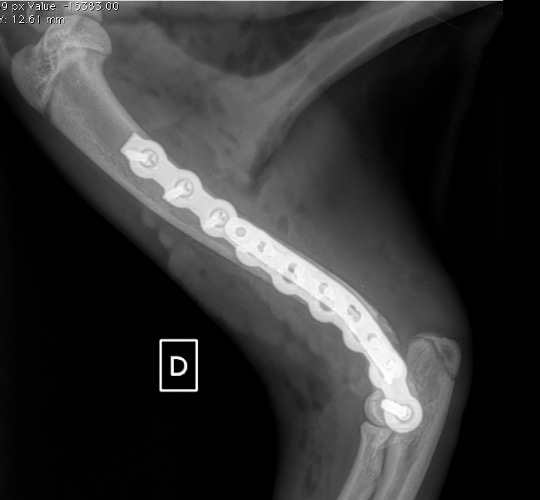

La réduction de ces fractures est rendue difficile par la présence de multiples fragments et l’instabilité inhérente à la présence du radius et de l’ulna distalement. L’objectif premier est d’assurer une réduction adéquate de la surface articulaire via une vis intracondylaire solide et de taille adéquate (environ 30 à 40% de la hauteur du condyle). Idéalement, cette vis est à incorporer au sein du trou distal de la plaque (exemple 1 et 2) car il s’agit du point d’ancrage le plus solide distalement. A défaut et de par sa cranialisation nécessaire, elle peut être placée en dehors du montage (exemple 3). De nombreuses divergences existent quant au placement de cette vis intracondylaire : historiquement placée en compression pour réduire au mieux la surface articulaire, elle est maintenant souvent placée en vis de position, conférant plus de résistance du montage. Après réduction de la fracture condylienne, de petites broches peuvent permettre de réduire la fracture si celle-ci est reconstructible. A défaut, une réduction sous plaque est réalisée.

L’avènement récent des plaques anatomiques constitue une nouvelle option dans le traitement de ces fractures : dans l’exemple 3 (chat Ragdoll), une plaque anatomique médiale de 2 mm acceptant des vis de 1,6 et 2 mm a été utilisée seule avec succès.

Exemple 3 :

Figure 10 : Opération